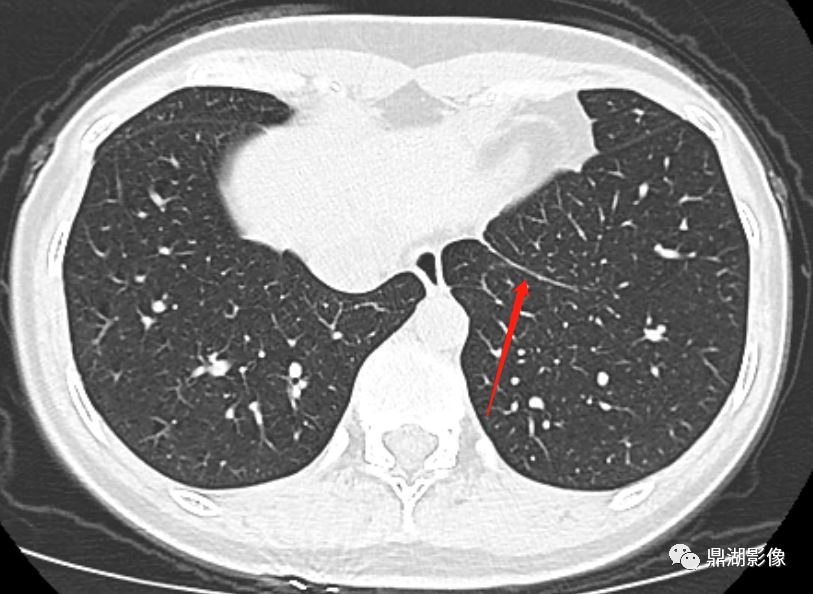

CT表现:沿肺门的下缘(肺静脉为肺门的最下端)延续的线样高密度,边缘光滑。 医学百科网 | YxBaike.Com

肺韧带深部的双侧段间分隔(A),注意右肺双分叉的T 形分隔即为9和10段的边界(箭头);(图片来源:格艾放射学) 医学百科网 | YxBaike.Com